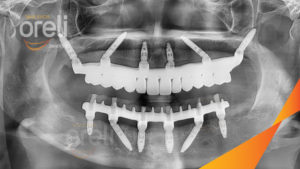

Cấy ghép răng Implant tại nha khoa Oreli

Cấy ghép nha khoa được sử dụng để gắn một cây cầu vĩnh viễn vào hàm.

Những cây cầu được giữ lại bằng cấy ghép này là một cải tiến lớn về sự phù hợp và chức năng so với răng giả tháo lắp, với lực cắn tăng 70%! Cấy ghép nha khoa tạo thành hệ thống chân răng tự nhiên cần thiết để củng cố và cải thiện lực cắn.